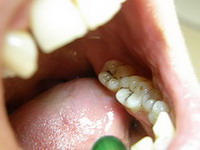

Carii pe molari

Obturatii fizionomice